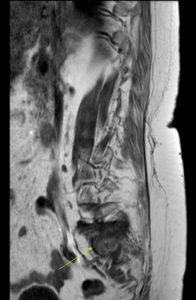

Figure 4: MRI showing sacral insufficiency fracture on background of osteoporosis and parathyroidectomy

Figure 5: MRI showing sacral insufficiency fracture on background of osteoporosis and parathyroidectomy

Figure 6: MRI showing sacral insufficiency fracture on background of osteoporosis and parathyroidectomy